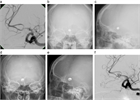

1. 未破裂脳動脈瘤の診断は、カテーテル法によるDSA:digital subtraction angiographyおよびその3次元血管撮影像がゴールドスタンダードである。3D-CTA:3次元ヘリカルコンピュータートモグラフィー、MRA: magnetic resonance angiographyなどは低侵襲な代替え診断法として未破裂脳動脈瘤の診断および治療に用いることが妥当である(推奨度1、J)